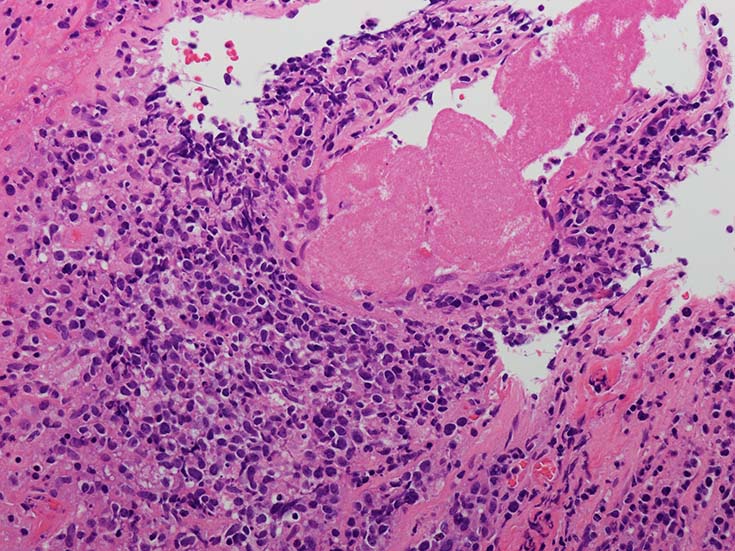

血管周囲性に大型類円形核や不整形核をもつ腫瘍細胞がシート状密に浸潤増殖している. Mitosisが多く認められる.細血管閉塞や破壊の所見がある.

間質にもシート状の腫瘍細胞浸潤がある. 大小 pleomorphicな傾向.(A, B). necrosisが認められる(C). 細気管支上皮直下まで密な浸潤あり, 小型リンパ球が混在している.(D)

血管中心性浸潤. 障害された血管内に血栓が形成されている.CD20陽性細胞がシート状密に浸潤, CD3陽性T細胞が多く混在している. EBER-ISH陽性 EBV感染細胞が多数認められ, >50 hpf, 定義より Grade3となる. 陽性細胞のサイズは大小さまざまであることに注意. Lymphomatoid granulomatosisの病態(WHO5thの診断では EBV-positive diffuse large B-cell lymphomaになる)をとっているが MTX-associated LPDの一型とするべき症例かもしれません.